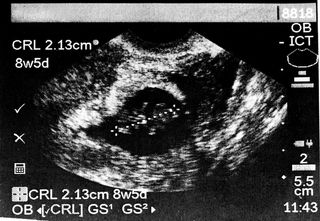

/https://static.texastribune.org/media/images/sonogram.jpg)